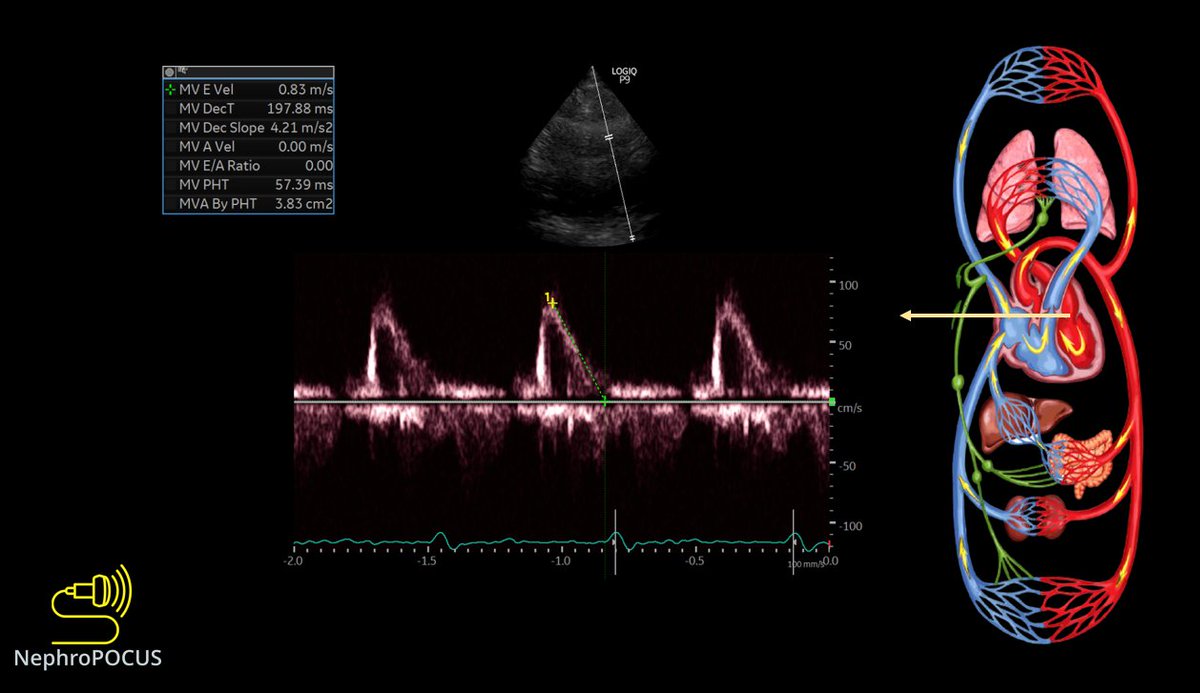

10/ Quick look at the left heart filling pressures using mitral inflow Doppler #POCUS and lateral annulus tissue Doppler.

E-wave deceleration time seems normal (an indicator of PCWP)